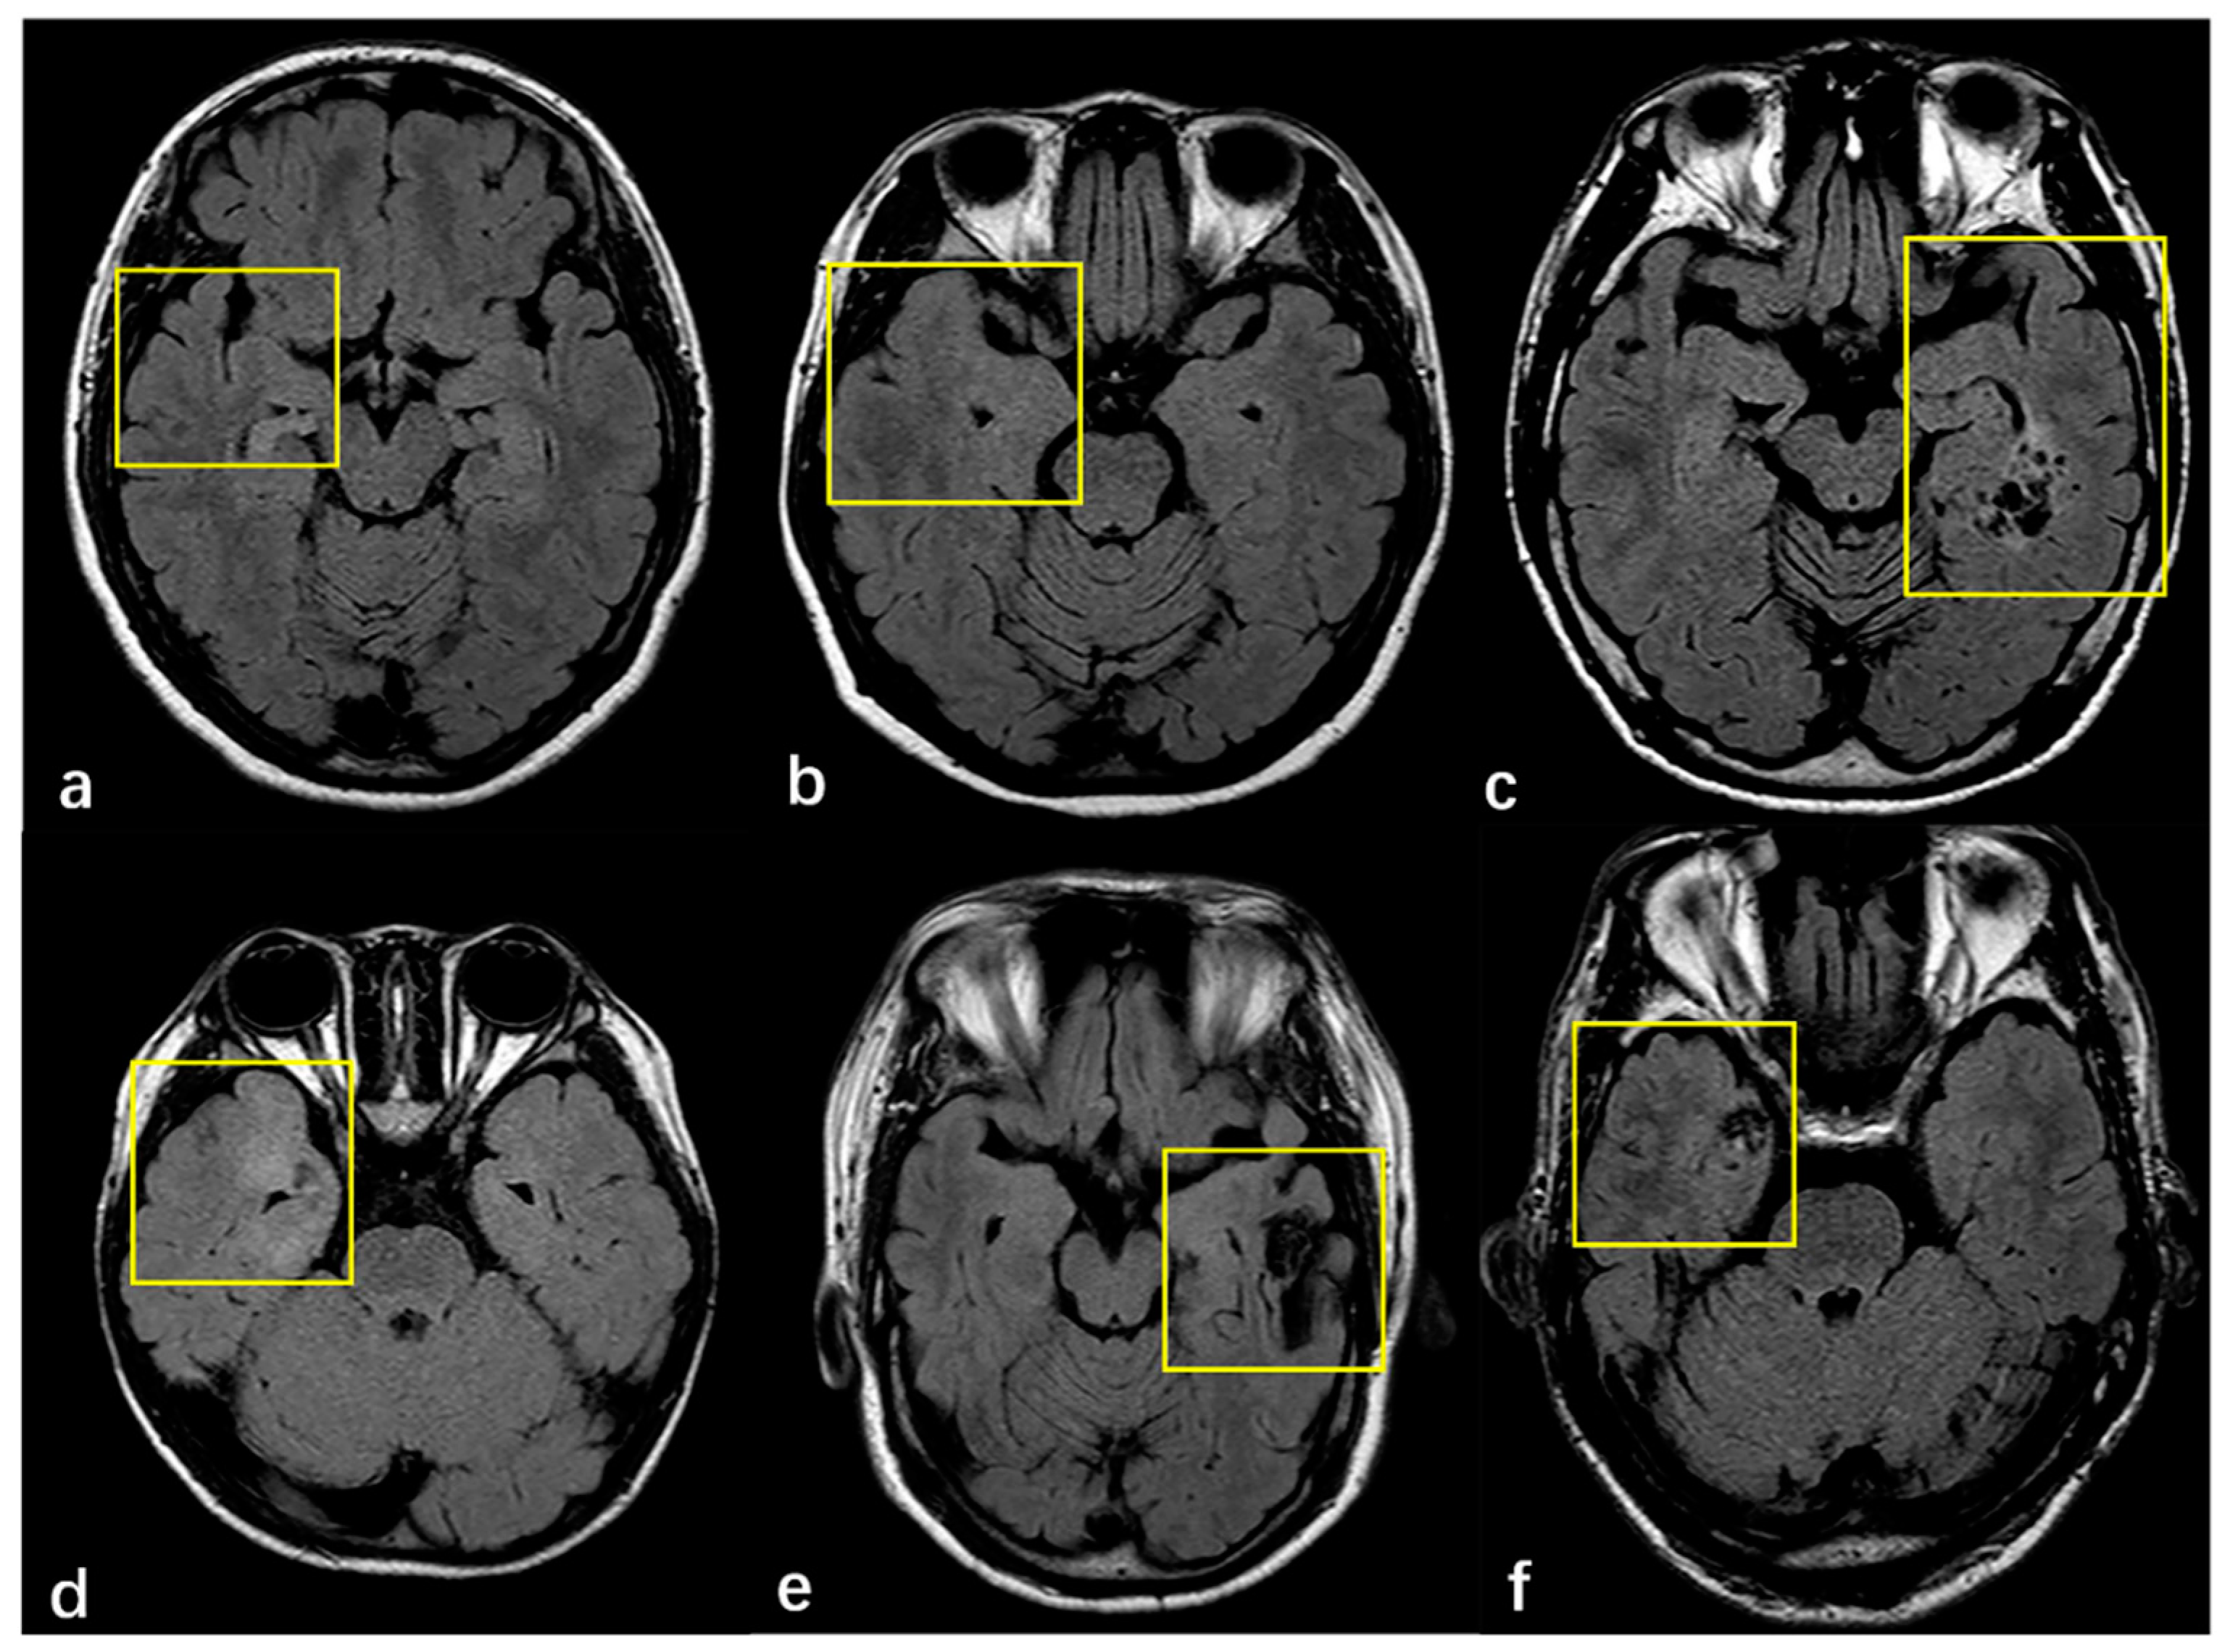

3.2. Radiologic and Pathology Findings

| MRI features of FCD | 0.680 | |||

| Cortex atrophy/thickening | 90 (13.5%) | 59 (13.4%) | 31 (13.8%) | |

| Indistinctness of the gray–white matter junction | 176 (66.2%) | 118(65.9%) | 58 (66.7%) | 1.000 |

| Intensity | 166 (62.4%) | 116 (64.8%) | 50 (57.5%) | 0.281 |

| MRI Negative | 36 (13.5%) | 19 (10.6%) | 17 (19.5%) | 0.056 |